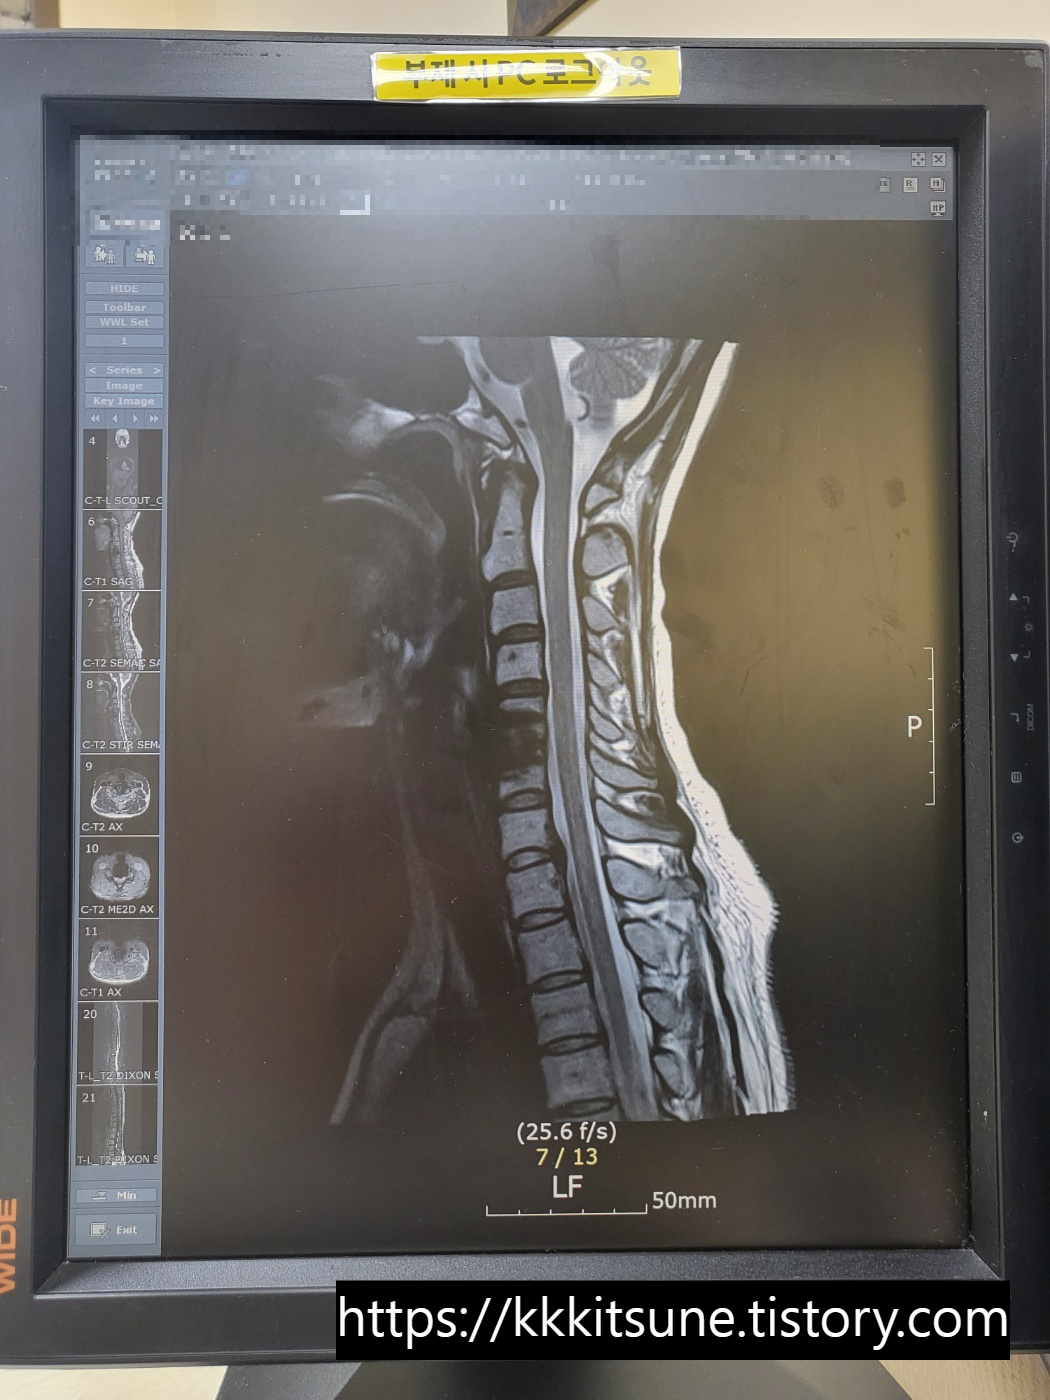

어제 찍은 MRI와 작년 수술 직전에 찍은 MRI를

비교해서 띄워주시면서 설명해 주셨다.

설명 없이 보기만 해도 차이가 너무 극명해서

진짜 다양한 감정이 교차했다.

왼쪽 사진에서는 튀어나온 디스크 때문에

신경이 거의 찔릴 뻔할 정도로 심각했다.

오른쪽 사진에서 뼈가 까맣게 뿌옇게 된 부분이

유합해서 고정시켜놓은 곳이다.

확실히 신경 길이 넓어지고 목이 일자로 펴졌다.

수술 전 사진이 누워서 찍은 MRI라는 것이

믿을 수 없을 정도로 역C자가 심한 것도 충격이었다.

-MRI 비교했더니 목이 일자로 펴짐

-수술 전에는 신경이 찔릴 뻔했는데 지금은 찌르는 부분 없어짐